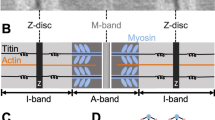

Human cardiomyopathy has been extensively studied in the last decade, and knowledge of the functional and structural alterations of the heart has grown. However, understanding of the pathogenesis has come mostly from experimental studies. A number of work have been designed to elucidate if alterations of the contractile apparatus of cardiac cells contribute to the impairment of heart mechanics in cardiomyopathies. As well, an important question is to be solved: whether energy supply of the contraction-relaxation cycle is sufficient in the myopathic heart. Use of cardiac fibers skinned by different techniques allows to evaluate functional ability of myofibrils, mitochondria and bound creatine kinase which plays an important role in cardiomyocyte energy metabolism. The data presented in this chapter show that experimental cardiomyopathies of various types have some common features. These are an increase in calcium sensitivity of myofibrils and a depression of functional activity of mitochondrial creatine kinase. Possible mechanisms and physiological significance of these changes are discussed.